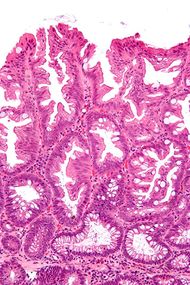

Sessile serrated adenoma 3 very high mag.jpg

صورة مجهرية لورم غدي مشرشر مفلح.

تشخص الأورام الغدية المشرشرة المفلطحة بظهورها المجهري؛ هستولوجياً، تتميز (1) بالتمدد القاعدي للخبايا، (2) تشرشر الخبايا القاعدية، (3) الخبايا الممتدة أفقياً حتى الغشاء القاعدي (الخبايا الأفقية)، و(4) تفرع الخبايا. أكثر الخصائص هذه الخصائص شيوعاً هو التمدد الجانبي للخبايا.

على عكس الأورام الغدية القولونية التقليدية، (مثل الورم الغدي الأنبوبي، الورم الغدي الزغبي)، ليس لديها (عادة) تغيرات نووية (فرط الانصباغ النووي، الاحتشاد النووي، النوية ذات الشكل البيضاوي/شكل السيجار).